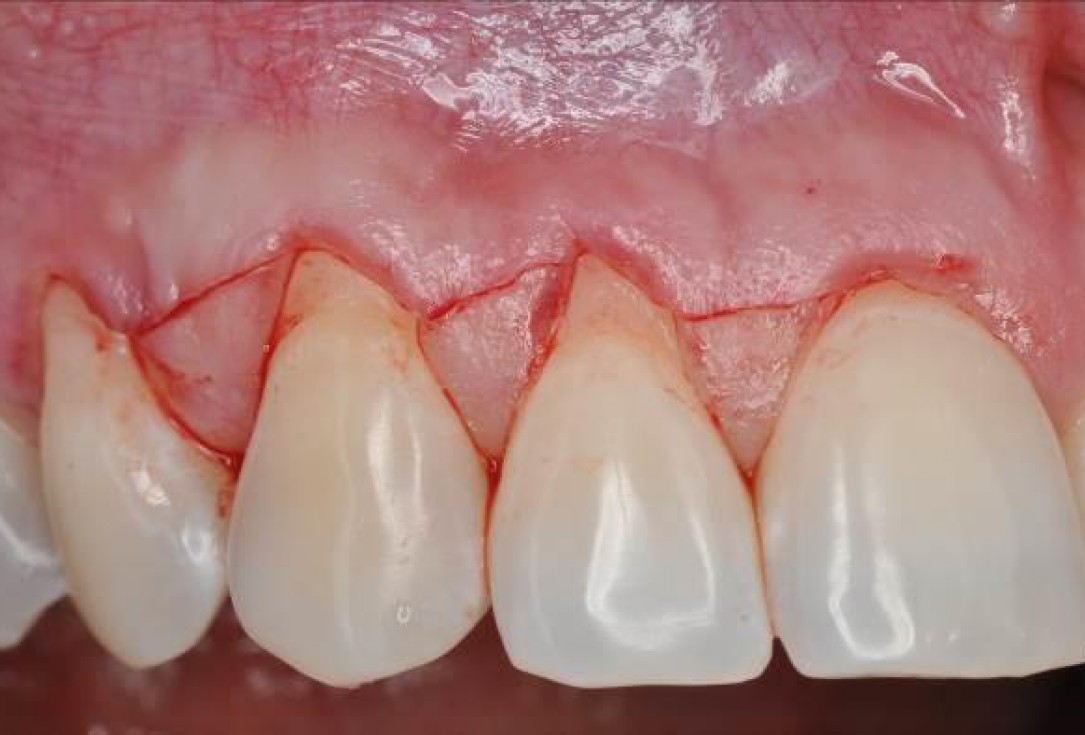

02/06 - Oblique incisions according to the modified coronally advanced flap technique (Zucchelli & De Sanctis J Periodontol. 2000).Multiple gingival recessions treated with the modified coronally advanced flap in conjunction with mucoderm® and Straumann® Emdogain® - Dr. D. B. Hangyási